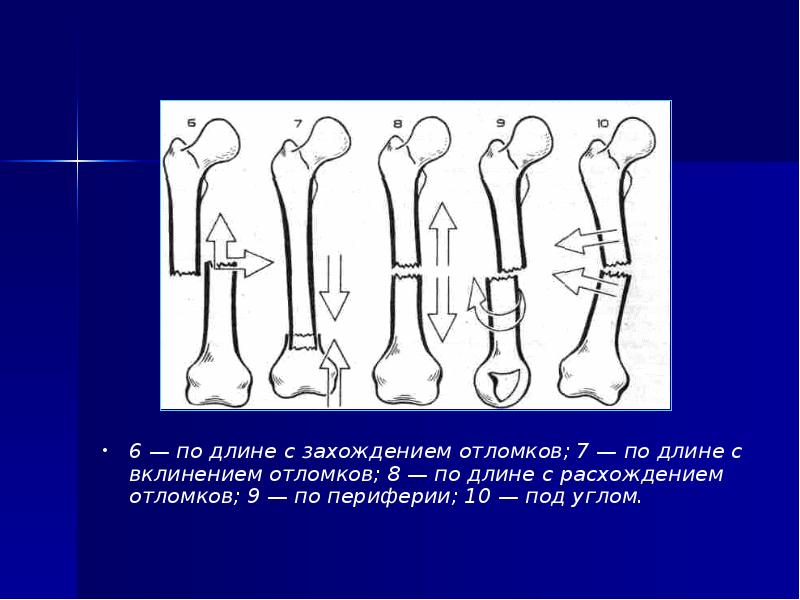

17. Смещения фрагментов

6 — по длине с захождением отломков; 7 — по длине с

вклинением отломков; 8 — по длине с расхождением

отломков; 9 — по периферии; 10 — под углом.

• 6 — по длине с захождением отломков; 7 — по длине с

вклинением отломков; 8 — по длине с расхождением

отломков; 9 — по периферии; 10 — под углом.

Слайд 17

Описание слайда:

6 — по длине с захождением отломков; 7 — по длине с вклинением отломков; 8 — по длине с расхождением отломков; 9 — по периферии; 10 — под углом.